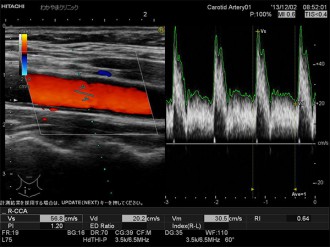

頸動脈の血管腔を観察します。総頸動脈の血管径は通常5~9mmです。

動脈硬化があると、血管がつまったり、狭小化したりします。エコーで観察し、治療方針などを検討します。